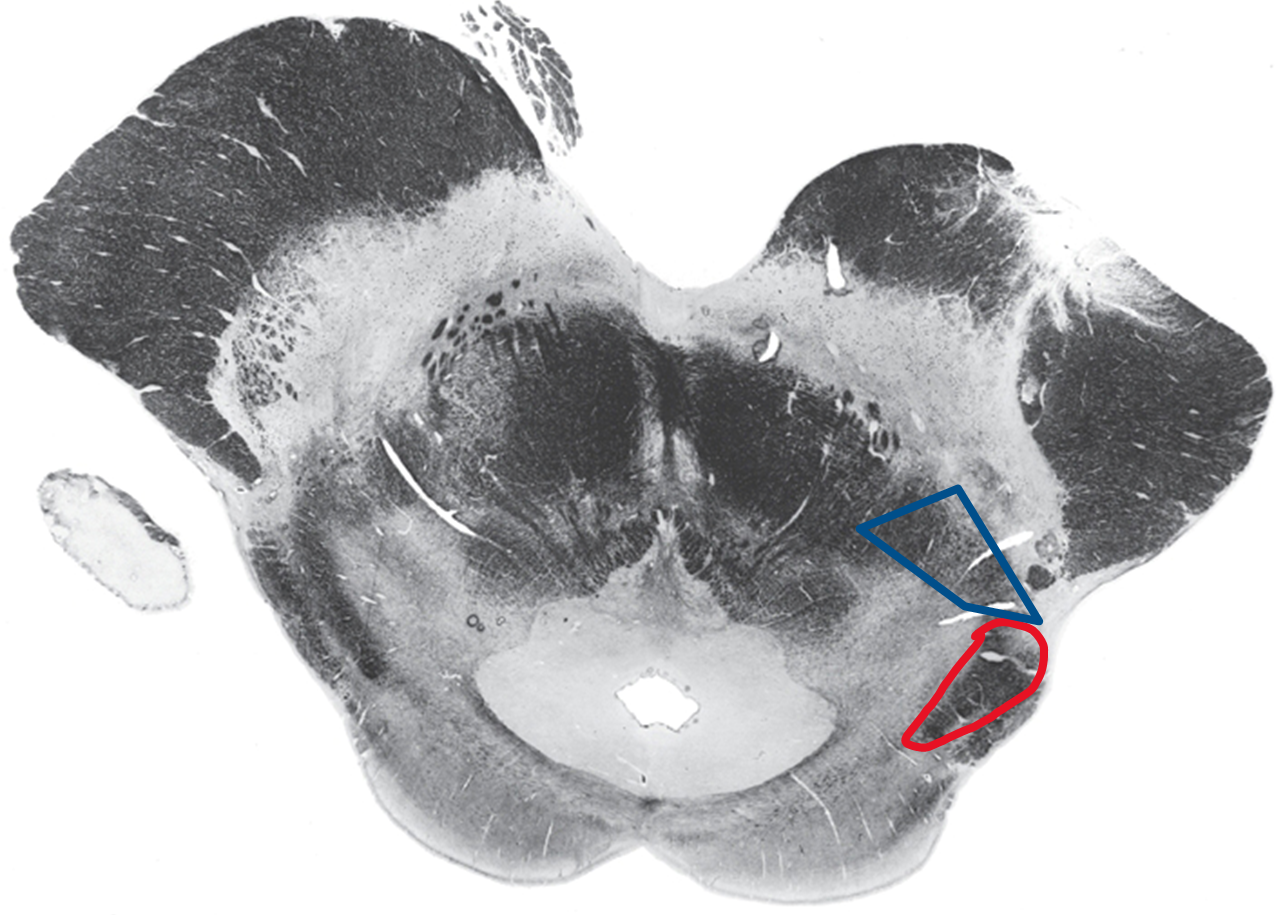

Lumbar spine

Blue DCML

Red ALS spinothalamic tract

Caudal medulla

Somatic sensory decussation

Blue DCML where dorsal column becomes medial lemniscus